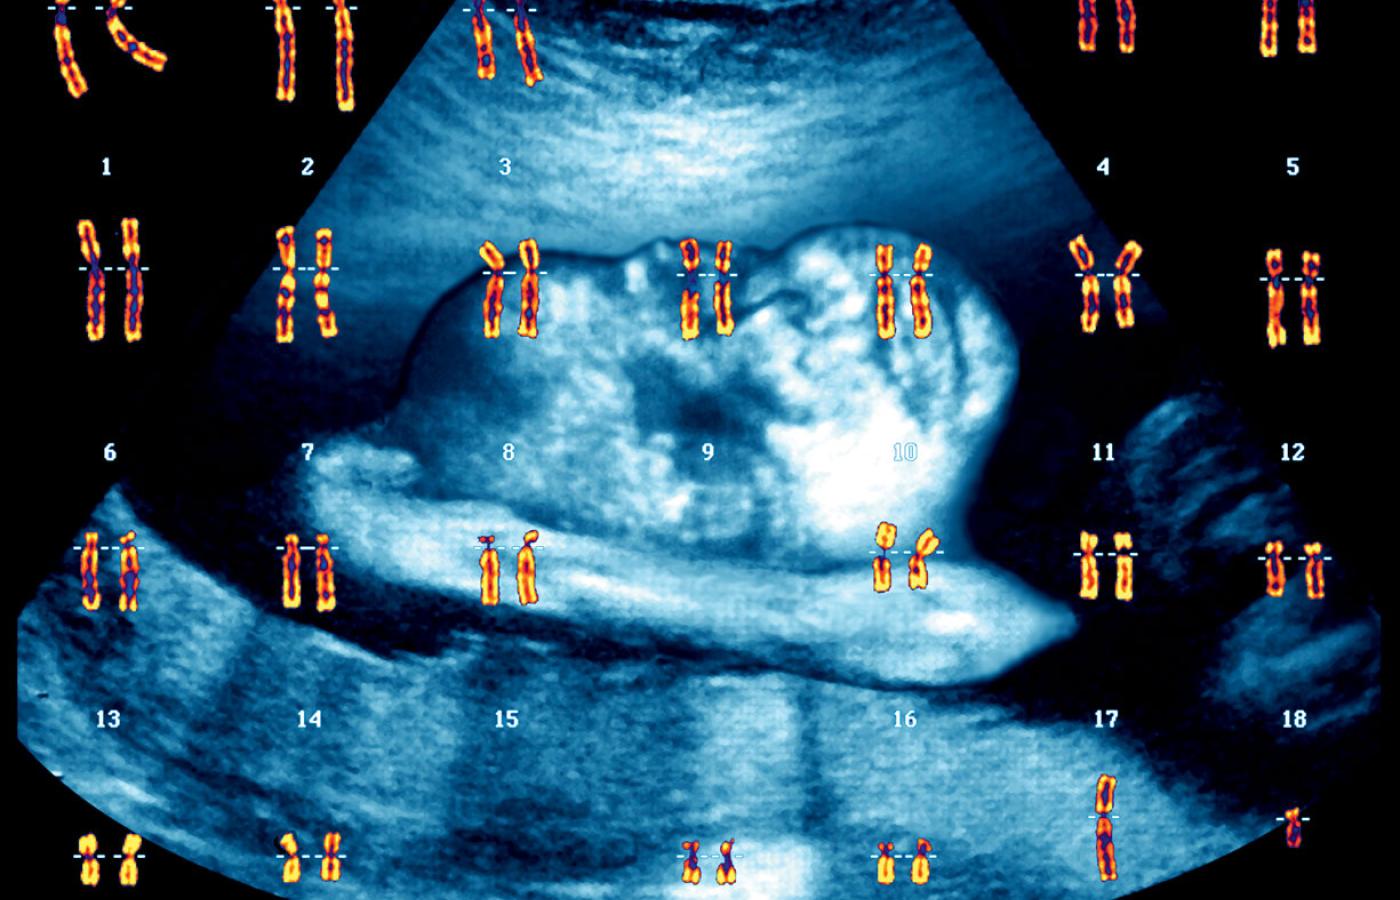

Będzie chłopczyk! Wizualizacja prezentuje pełny zestaw chromosomów, czyli tzw. kariotyp zdrowego mężczyzny (chromosom płci XY). W tle USG płodu. Będzie chłopczyk! Wizualizacja prezentuje pełny zestaw chromosomów, czyli tzw. kariotyp zdrowego mężczyzny (chromosom płci XY). W tle USG płodu. Zephyr/Science Photo Library / East News